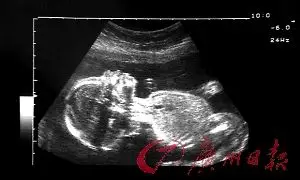

美国一项研究发现:女胎比男胎更容易胎死腹中